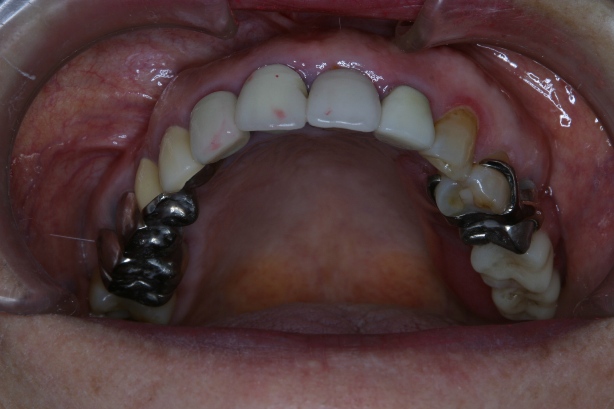

「8020運動」 表彰に出て頂いた方々のお口を拝見